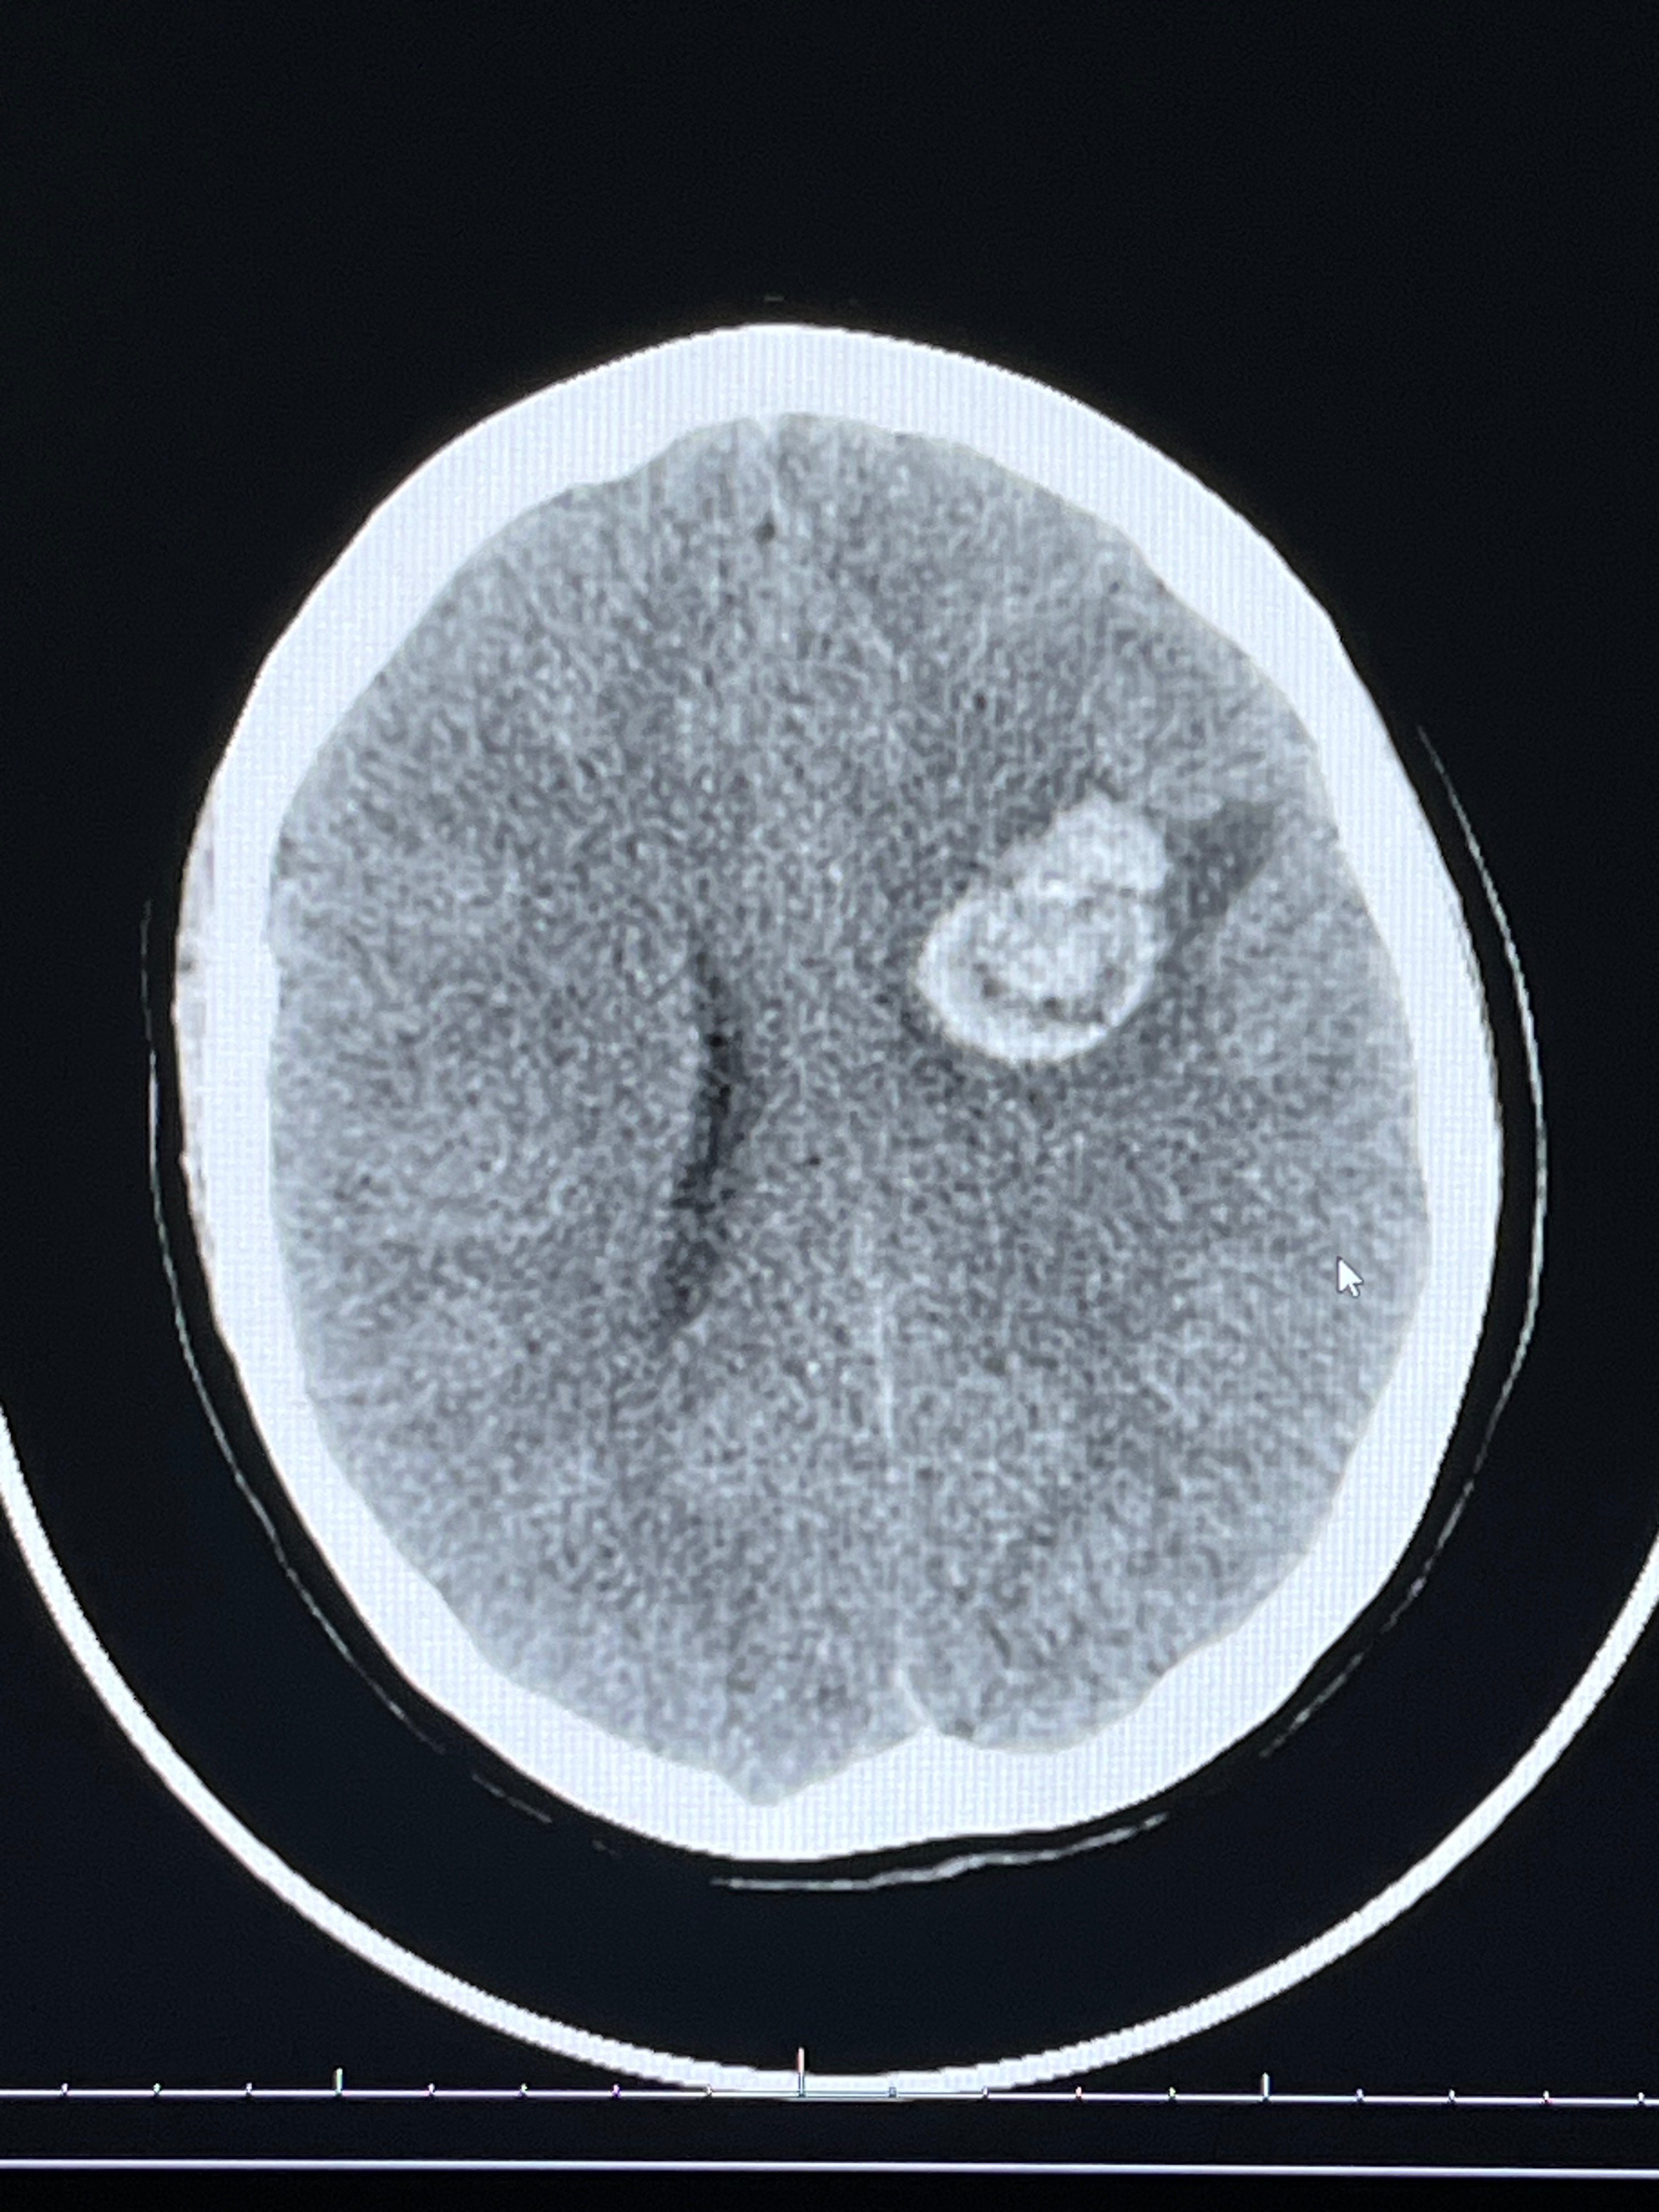

Serenity ultimately made the decision to go to the ER that night at midnight. They did a CT scan, MRI and also an Angiogram. On the scans they found that the mass was larger than it was previously when she was admitted a week and a half ago.

They scheduled a craniotomy for the same day, Monday 6/23/25; for this procedure, Seren was on a breathing machine.. they removed part of her skull and made a half dollar sized opening that they can go in and evacuate the access blood around the mass. After the blood was removed, they did more testing to get a better image of the mass. It turns out, the mass was several vessels that were bleeding periodically, or bleed, stop, then bleed again, for who knows how long. Probably years. That were considered a cavernous malformation and it was sent away to get biopsies! They hope they were able to remove and fix, all the vessels that were bleeding in her brain. She is going to have follow up testing this week to view where the mass was and to see if there is any access vessels there that they may have missed. The doctors stated that this is something that she was probably born with.

Serenity had a follow up appointment yesterday for her two weeks post op. Dr Gardner said that there was a spot of tiny tangled vessels still in the brain that he could not reach. When he tried to remove it, this is what caused the seizure. But for her recovery, she is doing AMAZING! She will have an MRI scheduled in two months, is unable to drive for 6 months, and is off work for another 8 weeks (at least). She will be doing outpatient therapy for her right sided weakness of her arm and face.

The next appointment will be to follow up on these remaining vessels. If the vessels are still there and bleeding, it could grow and she could go through the same process all over again. So, he wants to keep a close eye on it and he may have to go back in, and remove it if needed.